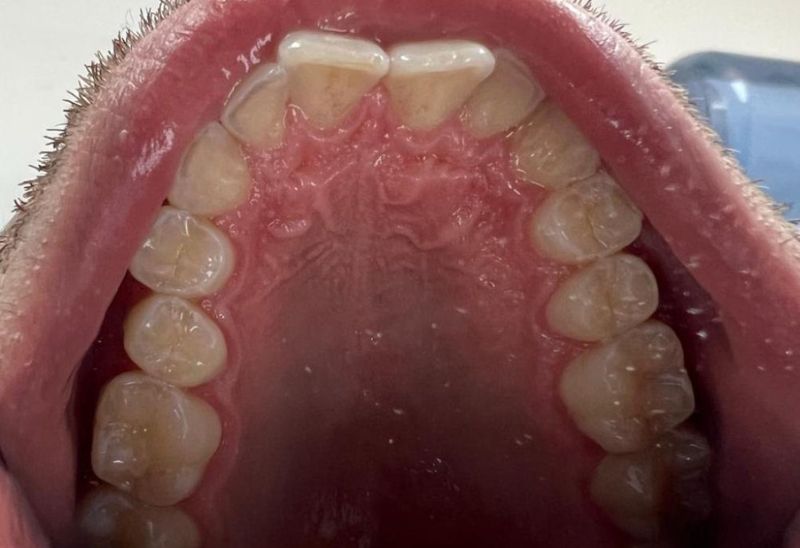

Prima e dopo l'apparecchio invisibile

In questa sezione mostreremo risultati reali ottenuti con l’ortodonzia invisibile a Roma. I cambiamenti riguardano non solo i denti, ma anche l’armonia del viso, la postura orale e l’autostima.